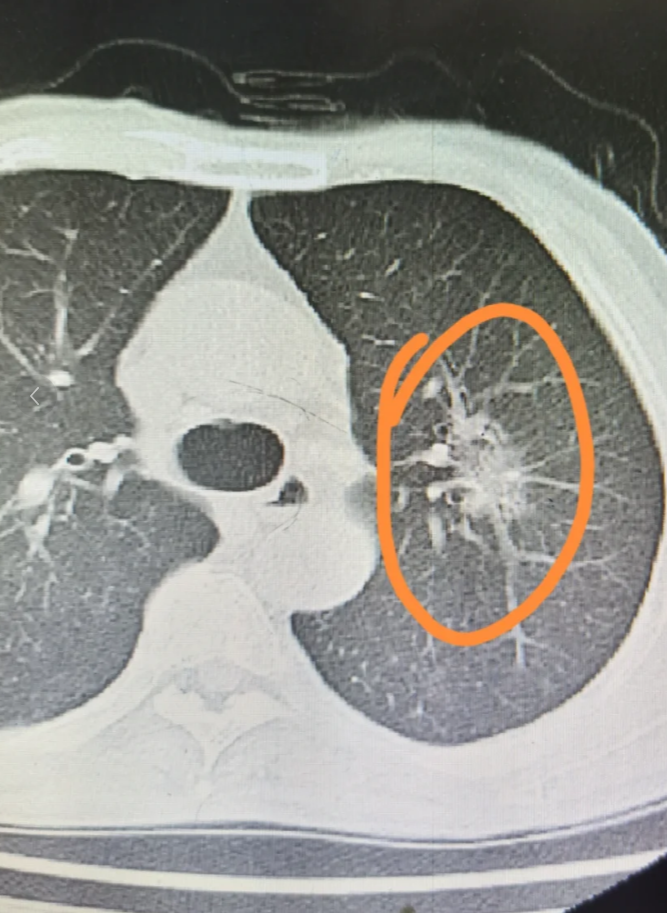

2、如果患者的结节较小边缘光滑,考虑为良性结节,需要定期复查,观察有无动态的改变如果患者的结节直径较大,边缘不光滑有毛刺征,临床上考虑为恶性结节可能性更大,需要完善肿瘤系列支气管镜结节穿刺活检,明确诊断当患者确诊为恶性结节时,需要跟根据病情给予手术治疗放疗化疗等等;右肺上叶小结节影的严重程度不能一概而论,需综合评估以下因素1 结节大小与恶性概率相关结节越大,恶性可能性越高小于5毫米的微小结节恶性概率较低510毫米结节恶性概率为6%28%大于20毫米结节恶性概率达64%82%但大小并非唯一指标,需结合其他特征判断2 结节形态提示恶性风险边缘不;右肺上叶纯磨玻璃结节存在一定癌变可能,但其风险与结节特征密切相关纯磨玻璃结节在CT影像中表现为肺内密度增高影,但内部血管和支气管结构仍可见其性质可能为良性如炎症出血或纤维化或恶性如肺腺癌恶性风险主要取决于以下特征结节大小直径小于5毫米的结节癌变风险较低510毫米者风。

3、右肺上叶后段磨玻璃密度结节是肺部影像学检查中发现的异常表现,其性质需结合多方面因素综合判断首先,年龄和吸烟史是重要的风险因素年龄较大或有长期吸烟史的人群,其结节恶性风险相对更高这是因为吸烟会导致肺部组织长期受有害物质刺激,增加细胞异常增生的可能性,进而提升恶性病变的发生率其次;右肺中上叶小结节的严重性需综合评估,不能一概而论以下情况需高度警惕恶性可能1结节大小直径大于8毫米尤其是超过20毫米的结节,恶性风险显著升高2形态特征边缘不规则呈分叶状有毛刺或胸膜牵拉征象时,提示恶性可能3内部结构结节内出现空泡空洞或钙化斑尤其是非均匀钙化,需进一步排查恶性;需通过增强CTPETCT或穿刺活检进一步确诊,早期手术切除可显著提高生存率处理原则发现右肺上叶前段小结节后,应结合病史症状及影像学特征进行初步判断,并通过定期复查如36个月一次监测结节变化若结节存在恶性征象或持续增大,需及时进行病理学检查以明确诊断。

4、右肺多发结节且右肺上叶存在较大结节,可能与以下原因有关,需结合进一步检查综合判断1 感染性疾病肺炎肺结核等感染可导致肺部炎症反应,引发局部组织增生,形成多发结节其中,肺结核的结节多呈干酪样坏死,可能伴随钙化细菌性肺炎的结节则以炎性浸润为主,通常伴有发热咳嗽等症状2 肉芽肿;腺癌是肺癌病理分型最多的肺癌,据统计,能占肺癌总量的70%80%,因此右肺上叶的腺癌是肺癌中较常见的病理分型右肺上叶腺癌是否严重,一方面取决于病理分型,另一方面取决于分期早晚及分化程度,即恶性程度如果是早期腺癌,经过积极治疗,治愈率和手术治疗后的存活率较高,5年存活率能达到90%甚至;CT检查发现右肺上叶小结节影,可能由多种原因引起,需结合结节特征和临床检查综合判断首先,结节性质可能为恶性或良性恶性病变常见于原发性肺癌或转移瘤,但概率相对较低良性病变包括错构瘤由正常组织异常组合形成炎性假瘤炎症后局部组织增生结核球结核菌感染后形成的干酪样坏死物包裹;家族肿瘤史,则需通过活检如穿刺或胸腔镜明确性质恶性结节治疗确诊为恶性肿瘤时,需尽早手术切除,并可能结合化疗放疗或靶向治疗,以降低转移风险注意事项右肺上叶小结节的恶性概率与结节特征密切相关,但仅凭影像学无法100%确定性质,因此需遵循医生建议,避免过度焦虑或延误治疗。